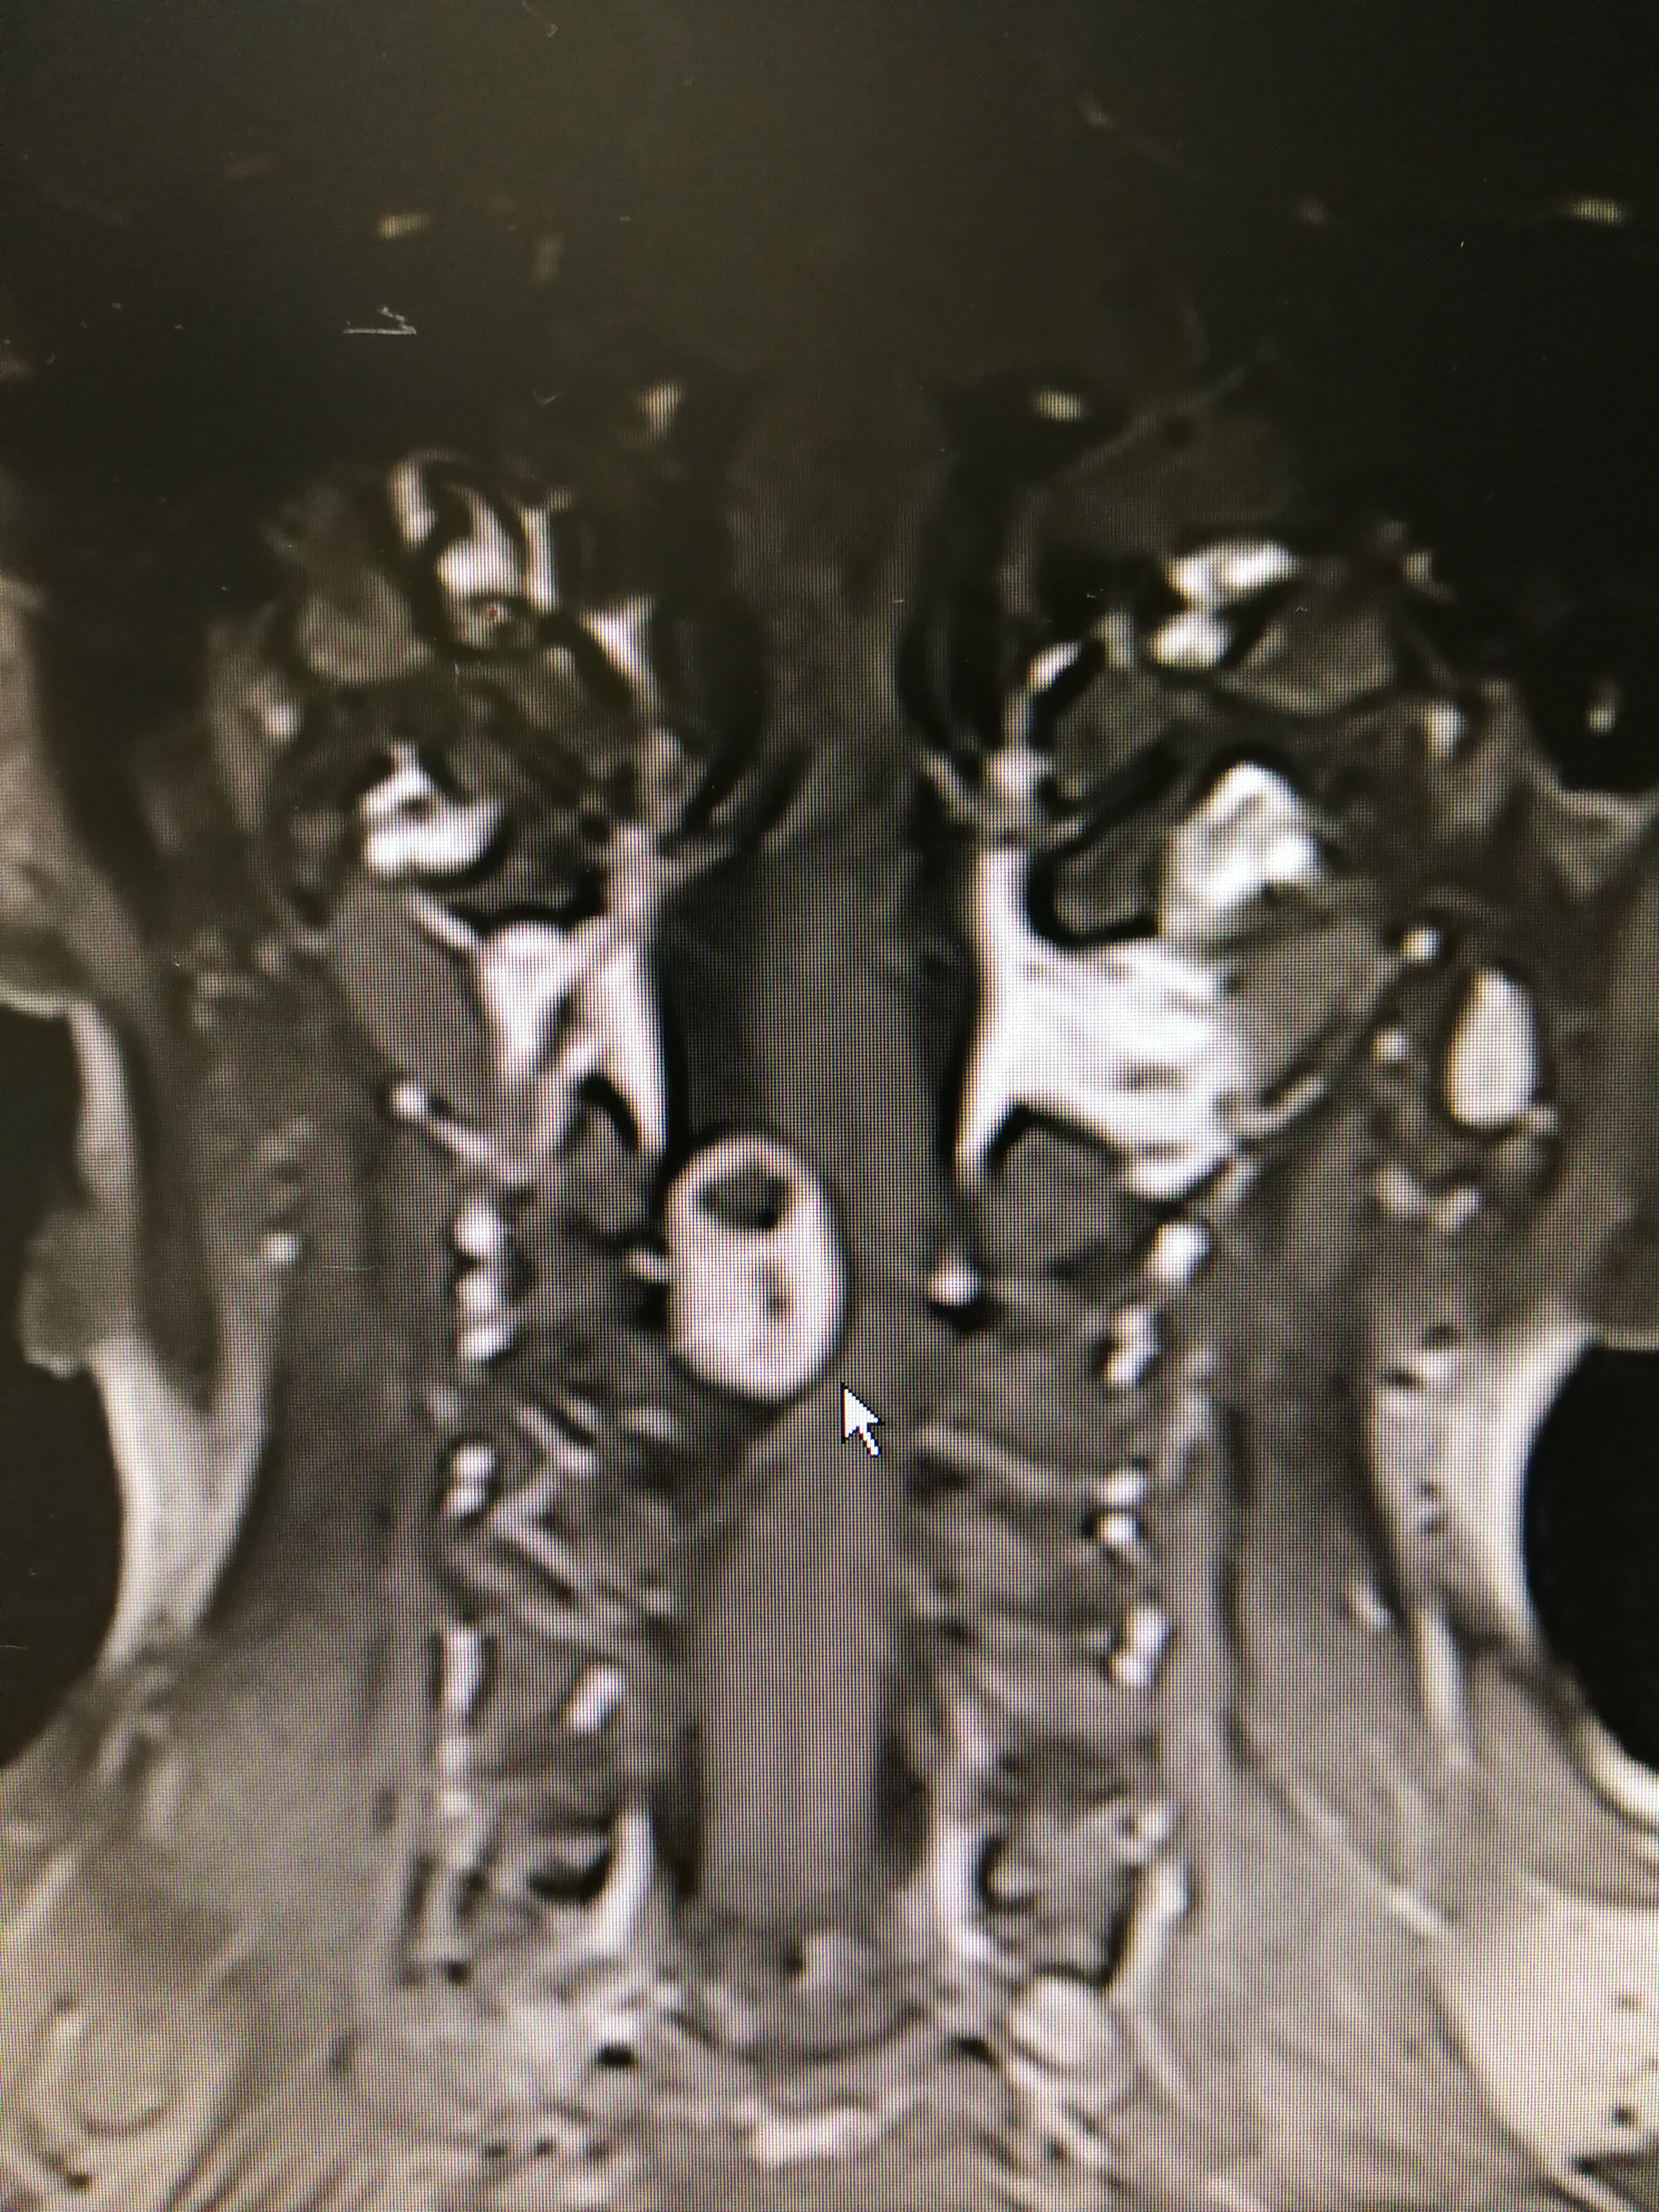

颈椎哑铃形肿瘤 女性50岁,双手麻木伴右侧上下肢无力2年

图片尺寸1502x1005